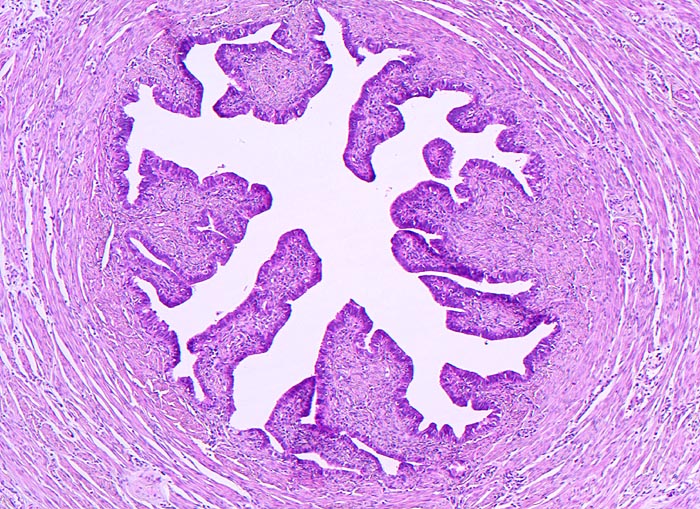

Tuba uterina

Normalbefund

Tuba uterina

Genitalorgane, weiblich

Tumorfreie Tube. Prominente Schleimhautfalten und sternförmiges Lumen. Aussen die zirkulär angeordnete glatte Muskelschicht.

Histologie

50